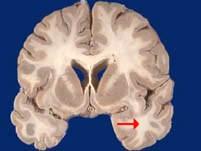

如图箭头所示为大脑哪个部位 ( )A、顶叶B、岛叶C、颞叶D、枕叶E、额叶一、单项选择题

问题 如图箭头所示为大脑哪个部位 ( )

选项 A、顶叶 B、岛叶 C、颞叶 D、枕叶 E、额叶 一、单项选择题

答案 C